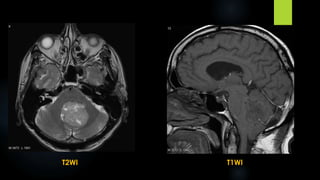

Ependymoma (contd.)

 MRI:

 The MR differentiation of ependymomas from other gliomas is related to their location &

morphology only.

 The post fossa ependymoma is lobulated soft tissue mass that appears to form a cast or mold

of the fourth ventricle & extrudes through its outlet foramina into the adjacent subarachnoid

cisterns

 The solid components are hypo – to isointense compared to brain on T1WI & hyperintense on

proton density & T2WI

 The cystic portions are slightly hyperintense to CSF on T1WI & hyperintense to brain on T2WI

 Intratumoral heterogeneity may represent necrosis , calcification , tumor vascularity or blood

degradation products

T2WI T1WI

T1 + C

FLAIR

DWI

 Differential diagnosis for ependymoma:

 Medulloblastoma

 Choroid plexus papilloma

 Central neurocytoma

 Pilocytic astrocytoma